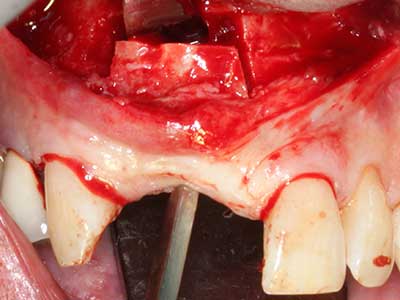

Piezo surgery has additional advantages when harvesting bone blocks. In addition to the high precision with osteotomy described above, the use of the thin saw tips specifically minimizes loss of material. Greater loss of material during harvesting can be expected with the thicker instrument tips, particularly when using Lindemann drills (Lakshmiganthan, Gokulanathan et al. 2012). The basal separation, which is necessary particularly for retromolar block transplants, is simplified by specially designed rectangular saws, with the result that piezo surgery is viewed as a precise, simple and safe procedure for harvesting retromolar bone blocks (Happe 2007) (Fig. 1-12).

Fig. 1: Preparation of a bone cover with the Piezomed (W&H Salzburg, Austria).

Fig. 2: Vertical and horizontal lateral maxillary defect with a high smile line with indication for pre-implant reconstruction.

Fig. 3: Basal separation of the block is easier with specially angled attachments.